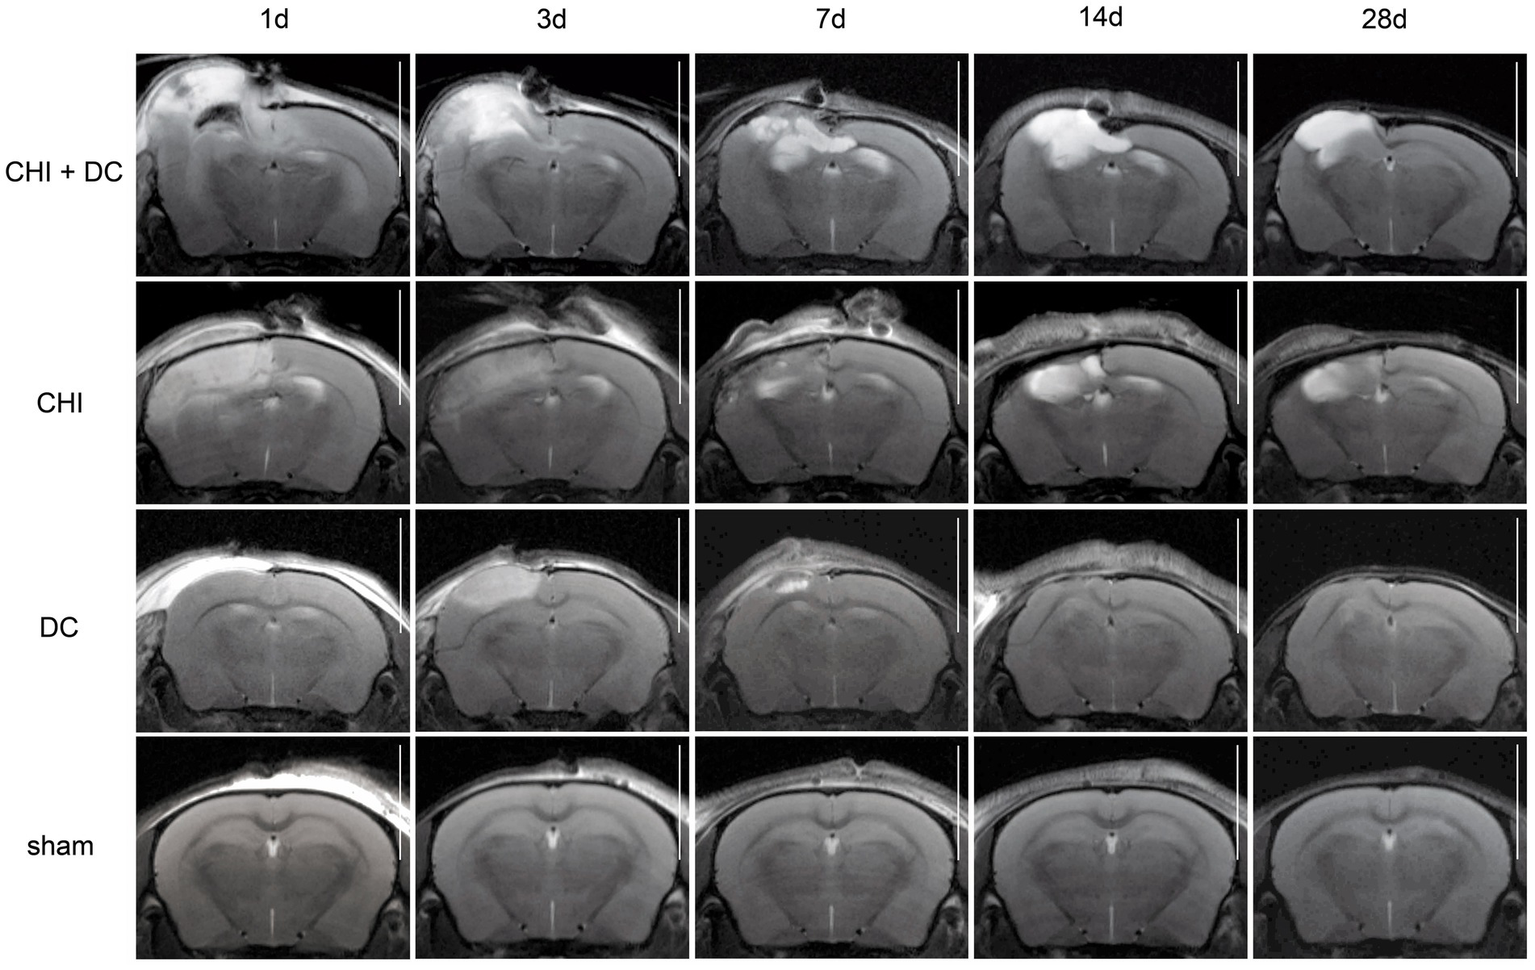

Figure 5

Panels of images representing the time course of radiological changes after trauma/decompressive craniectomy: time course (horizontal) vs. different treatment groups (vertical). Here, the MRI scans as T1-weighted images are presented. See description and interpretation of radiological changes in the main text. The scans were obtained in representative animals (each row demonstrates the radiological course in the same animal) using a 9.4 Tesla MRI scanner; white bar = 5 mm.

As expected, sham animals demonstrated no discernible brain damage (including no brain edema formation). During the postoperative course, only proper healing of the superficial scalp wound could be demonstrated.

In contrast, the DC group demonstrated slight deformation of the cortex areas underlying the skull window as early as 1d after surgery. Initially, only the superficial cortex layer demonstrated some hyperintensity in T2-scans. However, at this time point, a restriction of fluid diffusion (suggestive of cytotoxic edema) that reached more profound areas of the cortex could be displayed in ADC images. These changes faded over time point 3d and were accompanied by appearance of smaller, ADC-hyperintense areas that resolved at time point 14d up to 28d. However, some small ADC- (and, to lesser degree, T2-) hyperintense cortical and subcortical changes remained visible up to endpoint 28d, resulting in deformation of the region underlying the craniectomy. This could be visualized in T1 images as some distortion of anatomical structures (cortical areas, corpus callosum and hippocampal area). Notably, no signs of subgaleal CSF collection or changes specific for brain tissue infection could be noted in the DC group.

In the CHI group, the features of brain edema formation and parenchymal changes, typical for a murine CHI model, were displayed. Thus, an early peak of cerebral swelling (at 1d and 3d) could be demonstrated. Here, the area of increased water content was hyperintense in the T2 scan but hypointense in the ADC-weighted images, suggesting the cytotoxic character of edema. The accompanying midline shift indicated the space-occupying effect of edema. In the further course, the changes evolved to the form of ADC-mixed lesions with an increasing hyperintense component, most prominent 28d after injury.

The animals subjected to both trauma and decompression (CHI+DC) demonstrated the most striking injury pattern. Starting at the earliest time point (1d postinjury), massive swelling of the decompressed cortex, including external herniation of the cerebral tissue over the bone margin, was present. According to ADC mapping, the edema of the cortex was mostly of cytotoxic character (similar to the trauma-only group). However, at early stages, some ADC-hyperintense zones could be delineated in subcortical areas (from 1d up to 7d). Starting at 7d, the extent of external herniation subsided, and the diffuse edematous zones (initially hypointense in the ADC map) evolved into T2- and ADC-hyperintense areas, with the signal intensity increasing during the protracted course. At the same time, the subcortical hyperintense areas expanded, peaking in size and intensity at 14d with a subsequent decline toward the endpoint (28d).